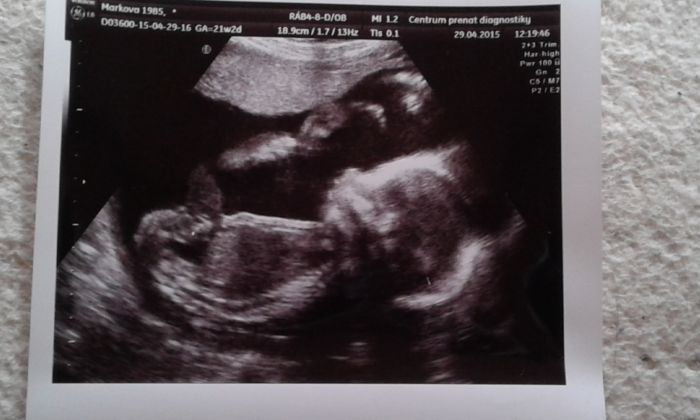

Ahoj maminky,omlouvam se ze jsem dlouho nepsal ale skoro 2 tydny jsem byl na hromade a tento tyden na antibiotikach tak sem nemel vubec silu spsat ale postupne sem vas docetl a gatuluju k zasnoubeni, novemu bydleni a vsem maaminkam k dobrym zpravam z kontrol a utz. Musim se pochlubit. Vcera jsme byli s Bobinkem a Pepinkou na 2 screeningu a pani doktorka nas ubezpacila ze je vse v poradku a tak jak ma ,coz nas neskutecne potesilo a sdelila nam ze to bude opravdu holcicka. Merime 24cm a azime 400g. Prilozim vam fotecku. Na kocarky oukame ale stale nemame favorita. Podlozku na monitorovanidechu bych rad koupil pro klid duse a gaky pro mrnouska. Bobinek rika ze se mimi ozyva a kope ale kdyz to chci takycitit tak mam vzdycky smulu. Ale urcite se dockam. Porad na ni mluvim a hladim brisko. Jak jste si uzili carodejnic? My opekli s rodici larky na zahrade a sli domu protoze zacalo posplichavat a taky mamina je unavena tak sla spat. Musi si odpocinout. Preji kresnou noc a zitra pekny prvni maj bez deste a mracku plny slunicka. Mejte se vas tatinek Dusik